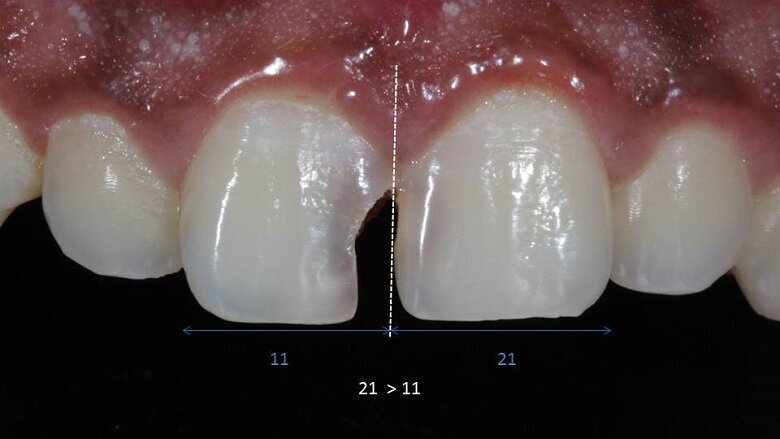

Vitality test was performed and the result was positive, thus no endodontic treatment was required. Pre-operative analysis showed that due to a longstanding decay on 11 , 21 tipped mesially. This resulted in a slight shift in midline (Fig 2). On measuring the mesio-distal width of both the central incisors, they showed a discrepancy (Fig 2).

Fig 2: mesial tipping of 21

Discrepancy in mesio-distal width

11